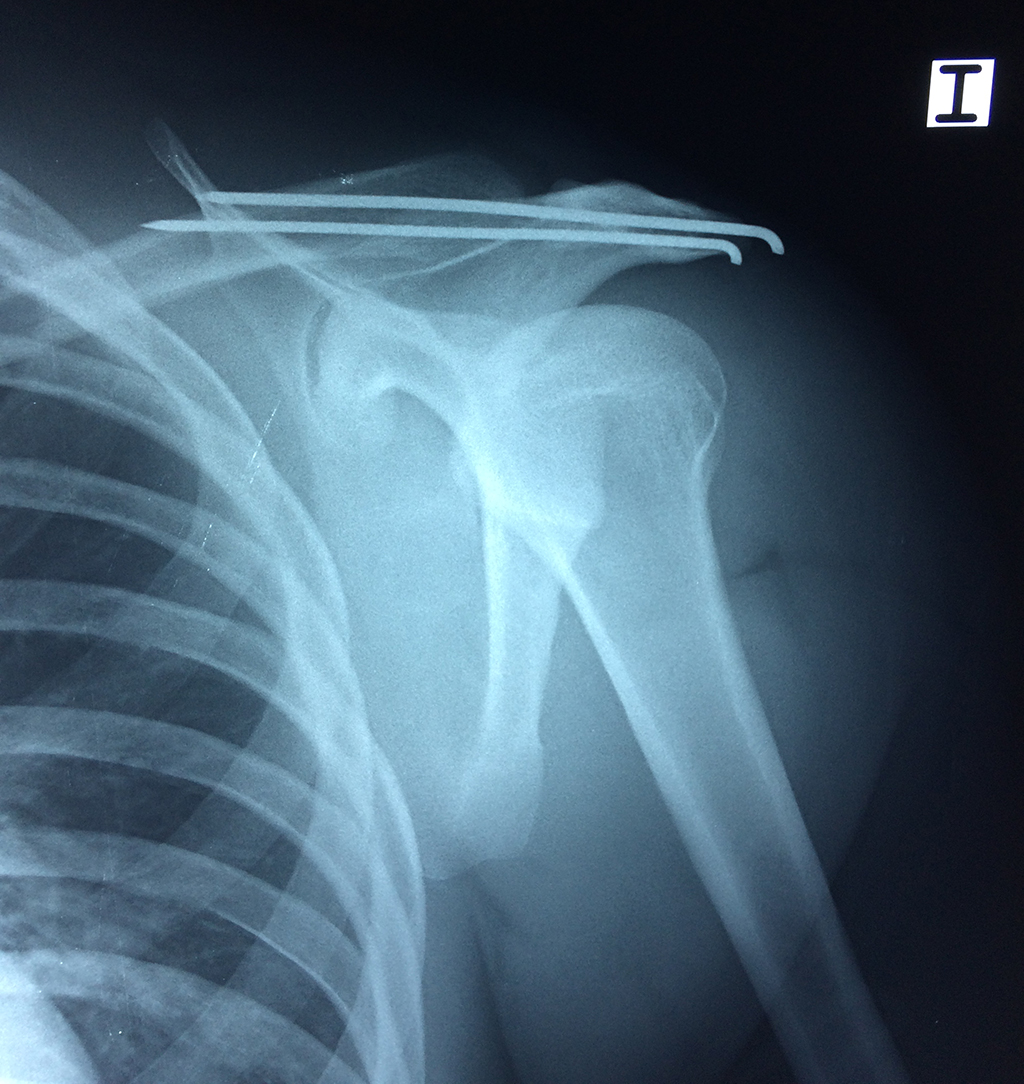

En anatomía humana, el hombro es la parte del cuerpo donde se une el brazo con el tronco. Está formado por la conjunción de los extremos de tres huesos: la clavícula, la escápula y el húmero; así como por músculos, ligamentos y tendones.

La principal articulación del hombro es la que une la cabeza del húmero con la escápula, recibe el nombre de articulación escapulohumeral y presenta dos superficies articulares, una de ellas corresponde a la cabeza del humero que tiene forma semiesférica y la otra es la cavidad glenoidea de la escápula, estas superficies están recubiertos por cartílago que permiten un movimiento suave e indoloro.

Exteriormente una envoltura de tejido blando circunda el conjunto, es la llamada cápsula articular que está reforzada por varios ligamentos que le dan estabilidad e impiden que los huesos se desplacen más allá de sus límites fisiológicos. Un conjunto de músculos y sus tendones se unen a las superficies de los huesos y hacen posible la movilidad de la articulación, entre ellos es muy importante el manguito rotador formado por cuatro músculos que proporcionan movilidad y estabilidad al hombro.